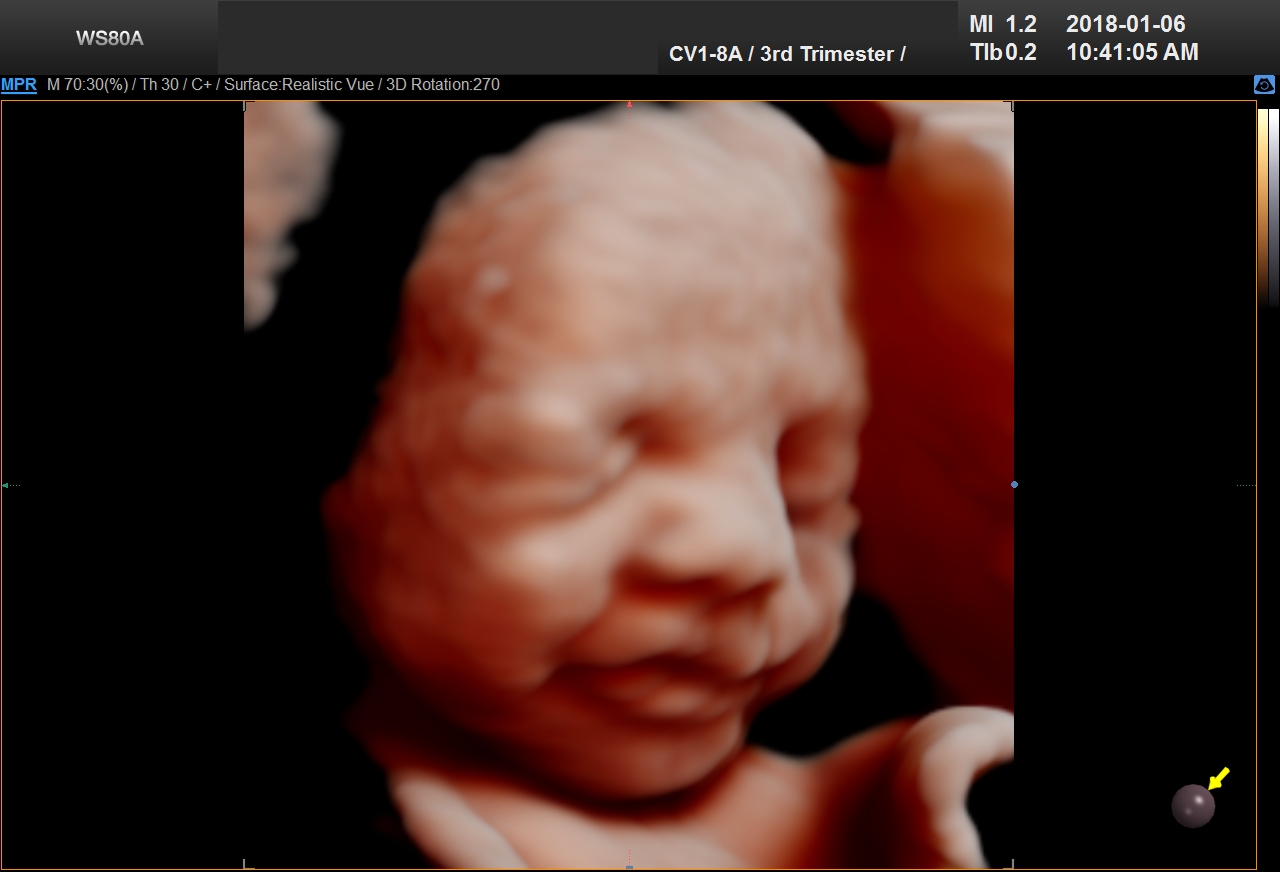

5D Ultrasound is the newest development in pregnancy imaging and it is patented by Samsung. It captures and combines high definition volume data to create automated images with amazing color and clarity. The bond between a new baby and the family gets even stronger when the family can view realistic pictures of baby in a 5D ultrasound.

UC Baby’s Latest 5D Ultrasound Service Offering

UC Baby Calgary is the first facility which brought cutting edge 5D technology to Canada. This cutting edge new ultrasound machine provides realistic pictures of the baby using the most advanced features of ultrasound imaging. We are offering high-definition 5D ultrasound technology to create unforgettable memories without extra cost. This new ultrasound technology allows families to bond stronger to the baby, with clear views of baby’s face and movements. With 5D technology, it is even possible to notice the dimples when baby smiles!

The best time to have a 5D ultrasound is between 24-32 weeks of pregnancy. Our experienced and professionally trained staff are there to amaze the mothers and their families. We also offer free online accounts for captured 2D, 3D, 4D and 5D images / videos in addition to free live broadcast of the whole ultrasound session. This is the fastest and easiest way to share baby’s first pictures and videos with friends and family instantly.